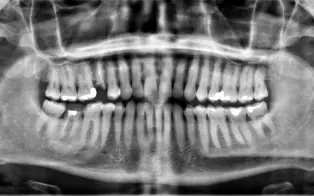

Fracture alveolo-dentaire